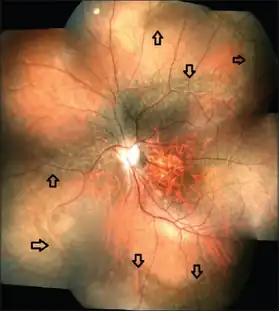

Many people with Stickler syndrome are very nearsighted (described as having high myopia) because of the shape of the eye. People with eye involvement are prone to increased pressure within the eye (ocular hypertension) which could lead to glaucoma and tearing or detachment of the light-sensitive retina of the eye (retinal detachment). Cataract may also present as an ocular complication associated with Stickler's Syndrome. The jelly-like substance within the eye (the vitreous humour) has a distinctive appearance in the types of Stickler syndrome associated with the COL2A1 and COL11A1 genes. As a result, regular appointments to a specialist ophthalmologist are advised. The type of Stickler syndrome associated with the COL11A2 gene does not affect the eye.[3]